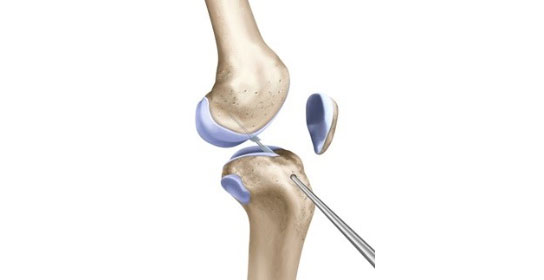

1. 관절경을 이용하여 인대의 위치와 손상 정도를 확인하고, 파열된 인대를 정리합니다.

2. 인대가 삽입될 터널 만들기 - 대퇴골과 경골에 이식건을 삽입할 구멍을 만듭니다.

3. 인대삽입 - 터널 구멍에 이식건을 통과시켜 연결 후 양쪽 뼈에 이식건을 고정하여 재건합니다. 타가건을 이용할 경우 잔존 인대조직을 덧대어 이식함으로써 회복을 앞당기고, 더욱 튼튼하게 재건되도록 돕습니다.

바른세상병원은 전방십자인대 재건술과 관련된 연구를 십여년간 지속하여 수술법을 개발해왔고, ‘잔존 인대 보존술식’과 ‘터널확장 방지 수술법’을 시행하고 있습니다. 잔존 조직을 최대한 보전해 이식건을 부착하는 재건술을 시행할 경우, 수술 후 무릎 관절의 고유 감각 기능을 유지할 수 있어 위치 감각 회복과 이식건의 자기 인대화 과정이 용이하기 때문에 안정성 향상은 물론 빠른 재활에 도움을 줄 수 있습니다.

최근에는 많은 병원에서 해당 수술법을 활용하고 있지만 바른세상병원은 2004년부터 이미 환자 치료에 도입해 왔고, 국내에서 독보적이라는 평가를 받고 있습니다. 또한 터널확장을 방지하는 안전한 수술법을 개발해서 시행하고 있으며, 관련 논문이 SCI급 학술지에 게재되기도 했습니다. 터널확장은 이식한 인대의 재파열 확률을 증가시키기 때문에 수술의 성패와 직결됩니다. 본원에서는 수술 중 터널 손상을 예방하기 위해 ‘관절 내 리머 적용법’과 ‘터널 내 골이식 방법’을 적용하여 재건술 후 터널확장을 방지하고 있습니다.해당 수술을 통해 본원에서 수술 받은 수천명의 환자들이 재파열 없이 운동을 하고 있습니다. 특히 일선에서 활동중인 운동종목 코치 및 감독들이 신뢰하는 병원으로, 많은 운동선수 또한 치료받고 회복하였습니다.